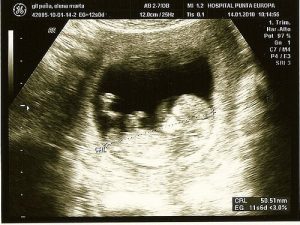

Ultraäänitutkimus on yleinen toimenpide, jonka avulla paitsi havaitaan mahdollisia sikiön terveysongelmia, myös saadaan ensimmäinen kuva vauvasta sekä selvitetään lapsen sukupuoli, vanhempien näin halutessa.

Ensimmäinen ultraäänitutkimus suoritetaan 10.-12. raskausviikon tienoilla. Tutkimuksessa tarkastetaan sikiön rakenne pääpiirteittäin ja mitataan sikiön niskaturvotus, joka toimii kromosomipoikkeavuuksien ja rakennepoikkeavuuksien riskin osoittajana. Tutkimuksissa on todettu, että alkuraskaudesta havaittu sikiön niskaturvotus on yhteydessä myös synnynnäisten sydänvikojen riskiin.

Jo ensimmäisessä ultraäänitutkimuksessa voidaan havaita suuret ja vaikeat rakennepoikkeavuudet. Jos tutkimus paljastaa korostuneen niskaturvotuksen tai epäilyn rakenteellisesta poikkeamasta, suoritetaan jatkotutkimuksia.

Tutkimus tehdään vatsanpeitteiden päältä tai emättimen kautta ultraäänilaitteen avulla. Laitteen avulla kuvaruudulle muodostetaan kuva korkeita ääniaaltoja, eli ultraääniä, hyväksi käyttäen. Ääniaallot eivät vahingoita sikiötä, mutta tarjoavat meille mahdollisuuden tarkkailla kohdun sisäistä elämää.